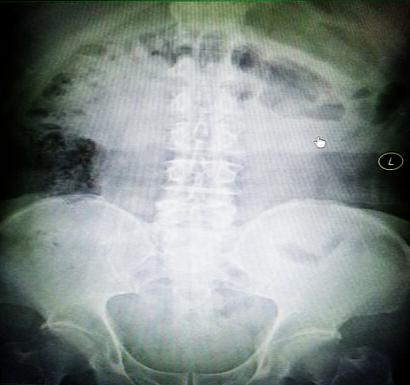

受試患者在結(jié)腸端端吻合術(shù)中,使用我司新研制產(chǎn)品達(dá)到了理想的預(yù)期效果?;颊咝g(shù)后7天、14天X光片顯影,可降解腸道支架均能按研制設(shè)計(jì)的預(yù)期時(shí)間節(jié)點(diǎn)保持應(yīng)有強(qiáng)度,術(shù)后21天X光片顯示可降解腸道支架已完全破碎,并排出體外。在整個(gè)試驗(yàn)過(guò)程中,病患無(wú)任何不良反映,耐受良好。